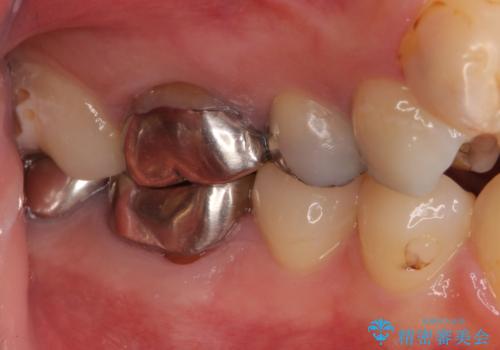

- 笑ったときに見てしまう上顎奥歯の銀歯を気にして来院された患者様です。

折角セラミッククラウンを装着するので、根管治療を行った後に補綴治療を行うこととしました。

他にも目立つ銀歯がありましたが、最も気にしている2本を優先して行うこととしました。

結婚式前にはクリーニングやホワイトニングを行い、その後他の歯を治療していく予定です。